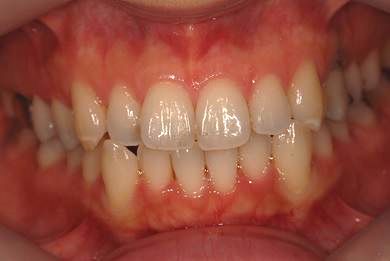

| 性別/年齢 | 女性 / 34歳 | ||||||||||||||||||||||||||||||||

| 主訴 | 以前虫歯を治療して金属を入れたところが、再び虫歯になったのか、軽くしみたり違和感がある。 | ||||||||||||||||||||||||||||||||

| 治療方針 | セラミック治療にて、審美的回復を行う。 | ||||||||||||||||||||||||||||||||

| 治療内容 | メタルボンドセラミッククラウン1本(メタルボンド用土台1本) | ||||||||||||||||||||||||||||||||

| 総治療費 | 125,685円 | ||||||||||||||||||||||||||||||||

| 治療期間 | 3ヶ月 |